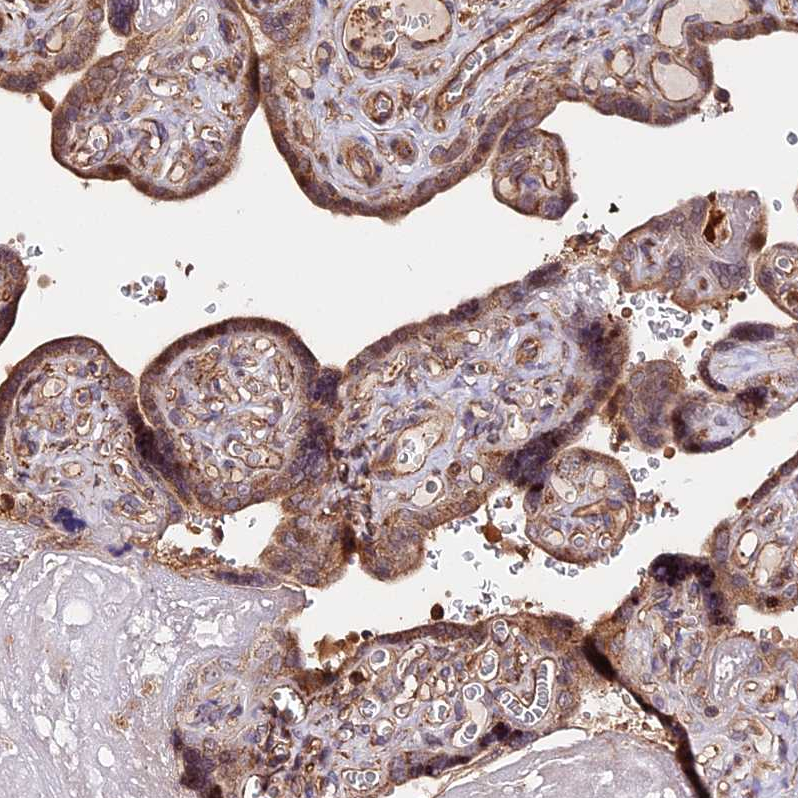

Immunohistochemical staining of human pancreas shows strong cytoplasm granular positivity in exocrine glandular cells.